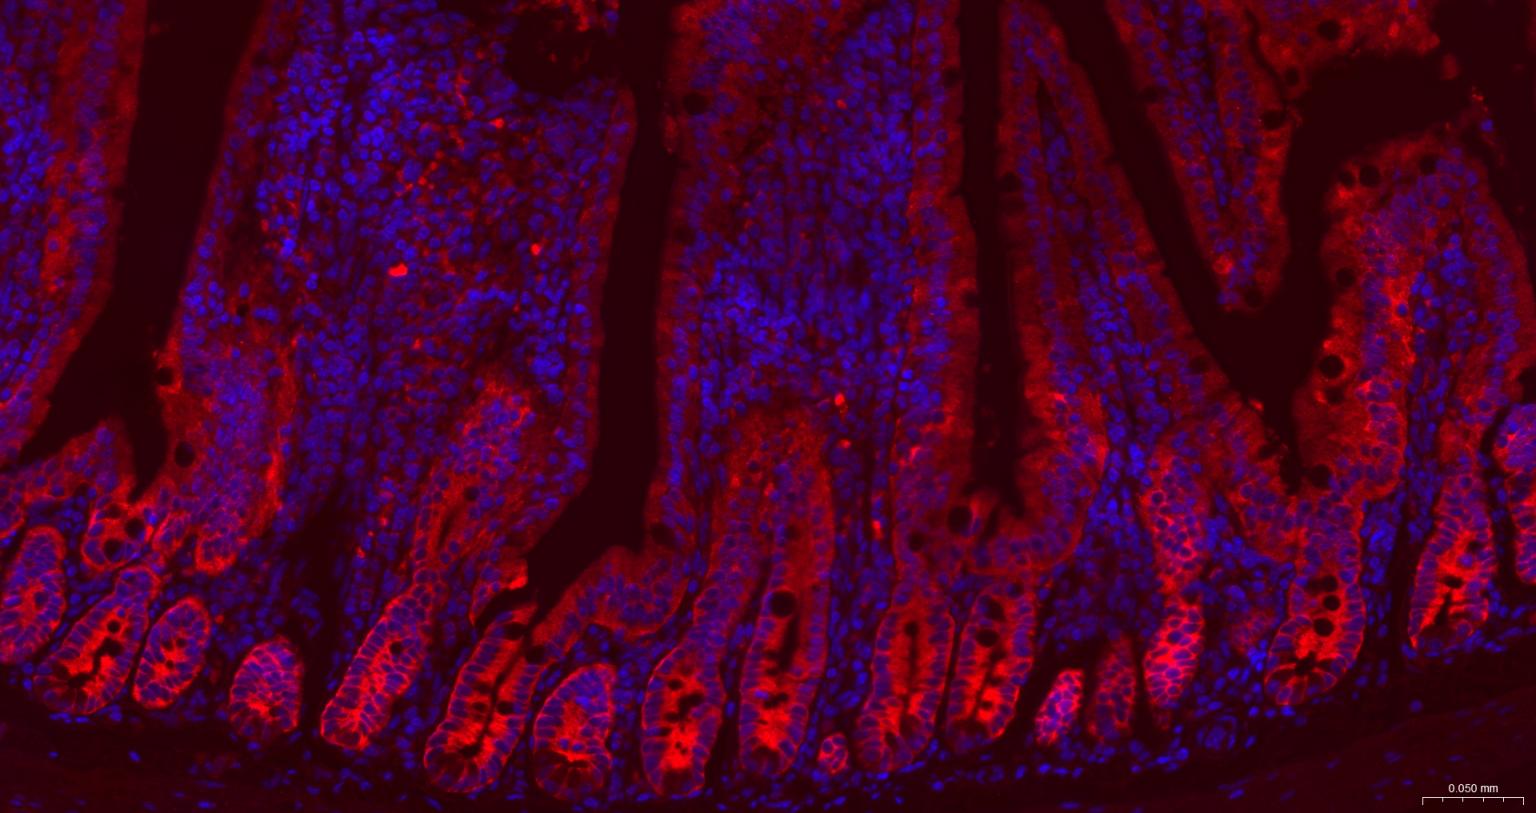

Paraformaldehyde-fixed, paraffin embedded Mouse Small Intestine; Antigen retrieval by boiling in sodium citrate buffer (pH6.0) for 15 min; The section was incubated with GART Monoclonal Antibody, Unconjugated (bsm-52537R) at 1:200 overnight at 4°C. Followed by conjugated Goat Anti-Rabbit IgG antibody (Red, bs-0295G-BF594), DAPI (blue, C02-04002) was used to stain the cell nuclei.

Paraformaldehyde-fixed, paraffin embedded Rat Small Intestine; Antigen retrieval by boiling in sodium citrate buffer (pH6.0) for 15 min; The section was incubated with GART Monoclonal Antibody, Unconjugated (bsm-52537R) at 1:200 overnight at 4°C. Followed by conjugated Goat Anti-Rabbit IgG antibody (Red, bs-0295G-BF594), DAPI (blue, C02-04002) was used to stain the cell nuclei.